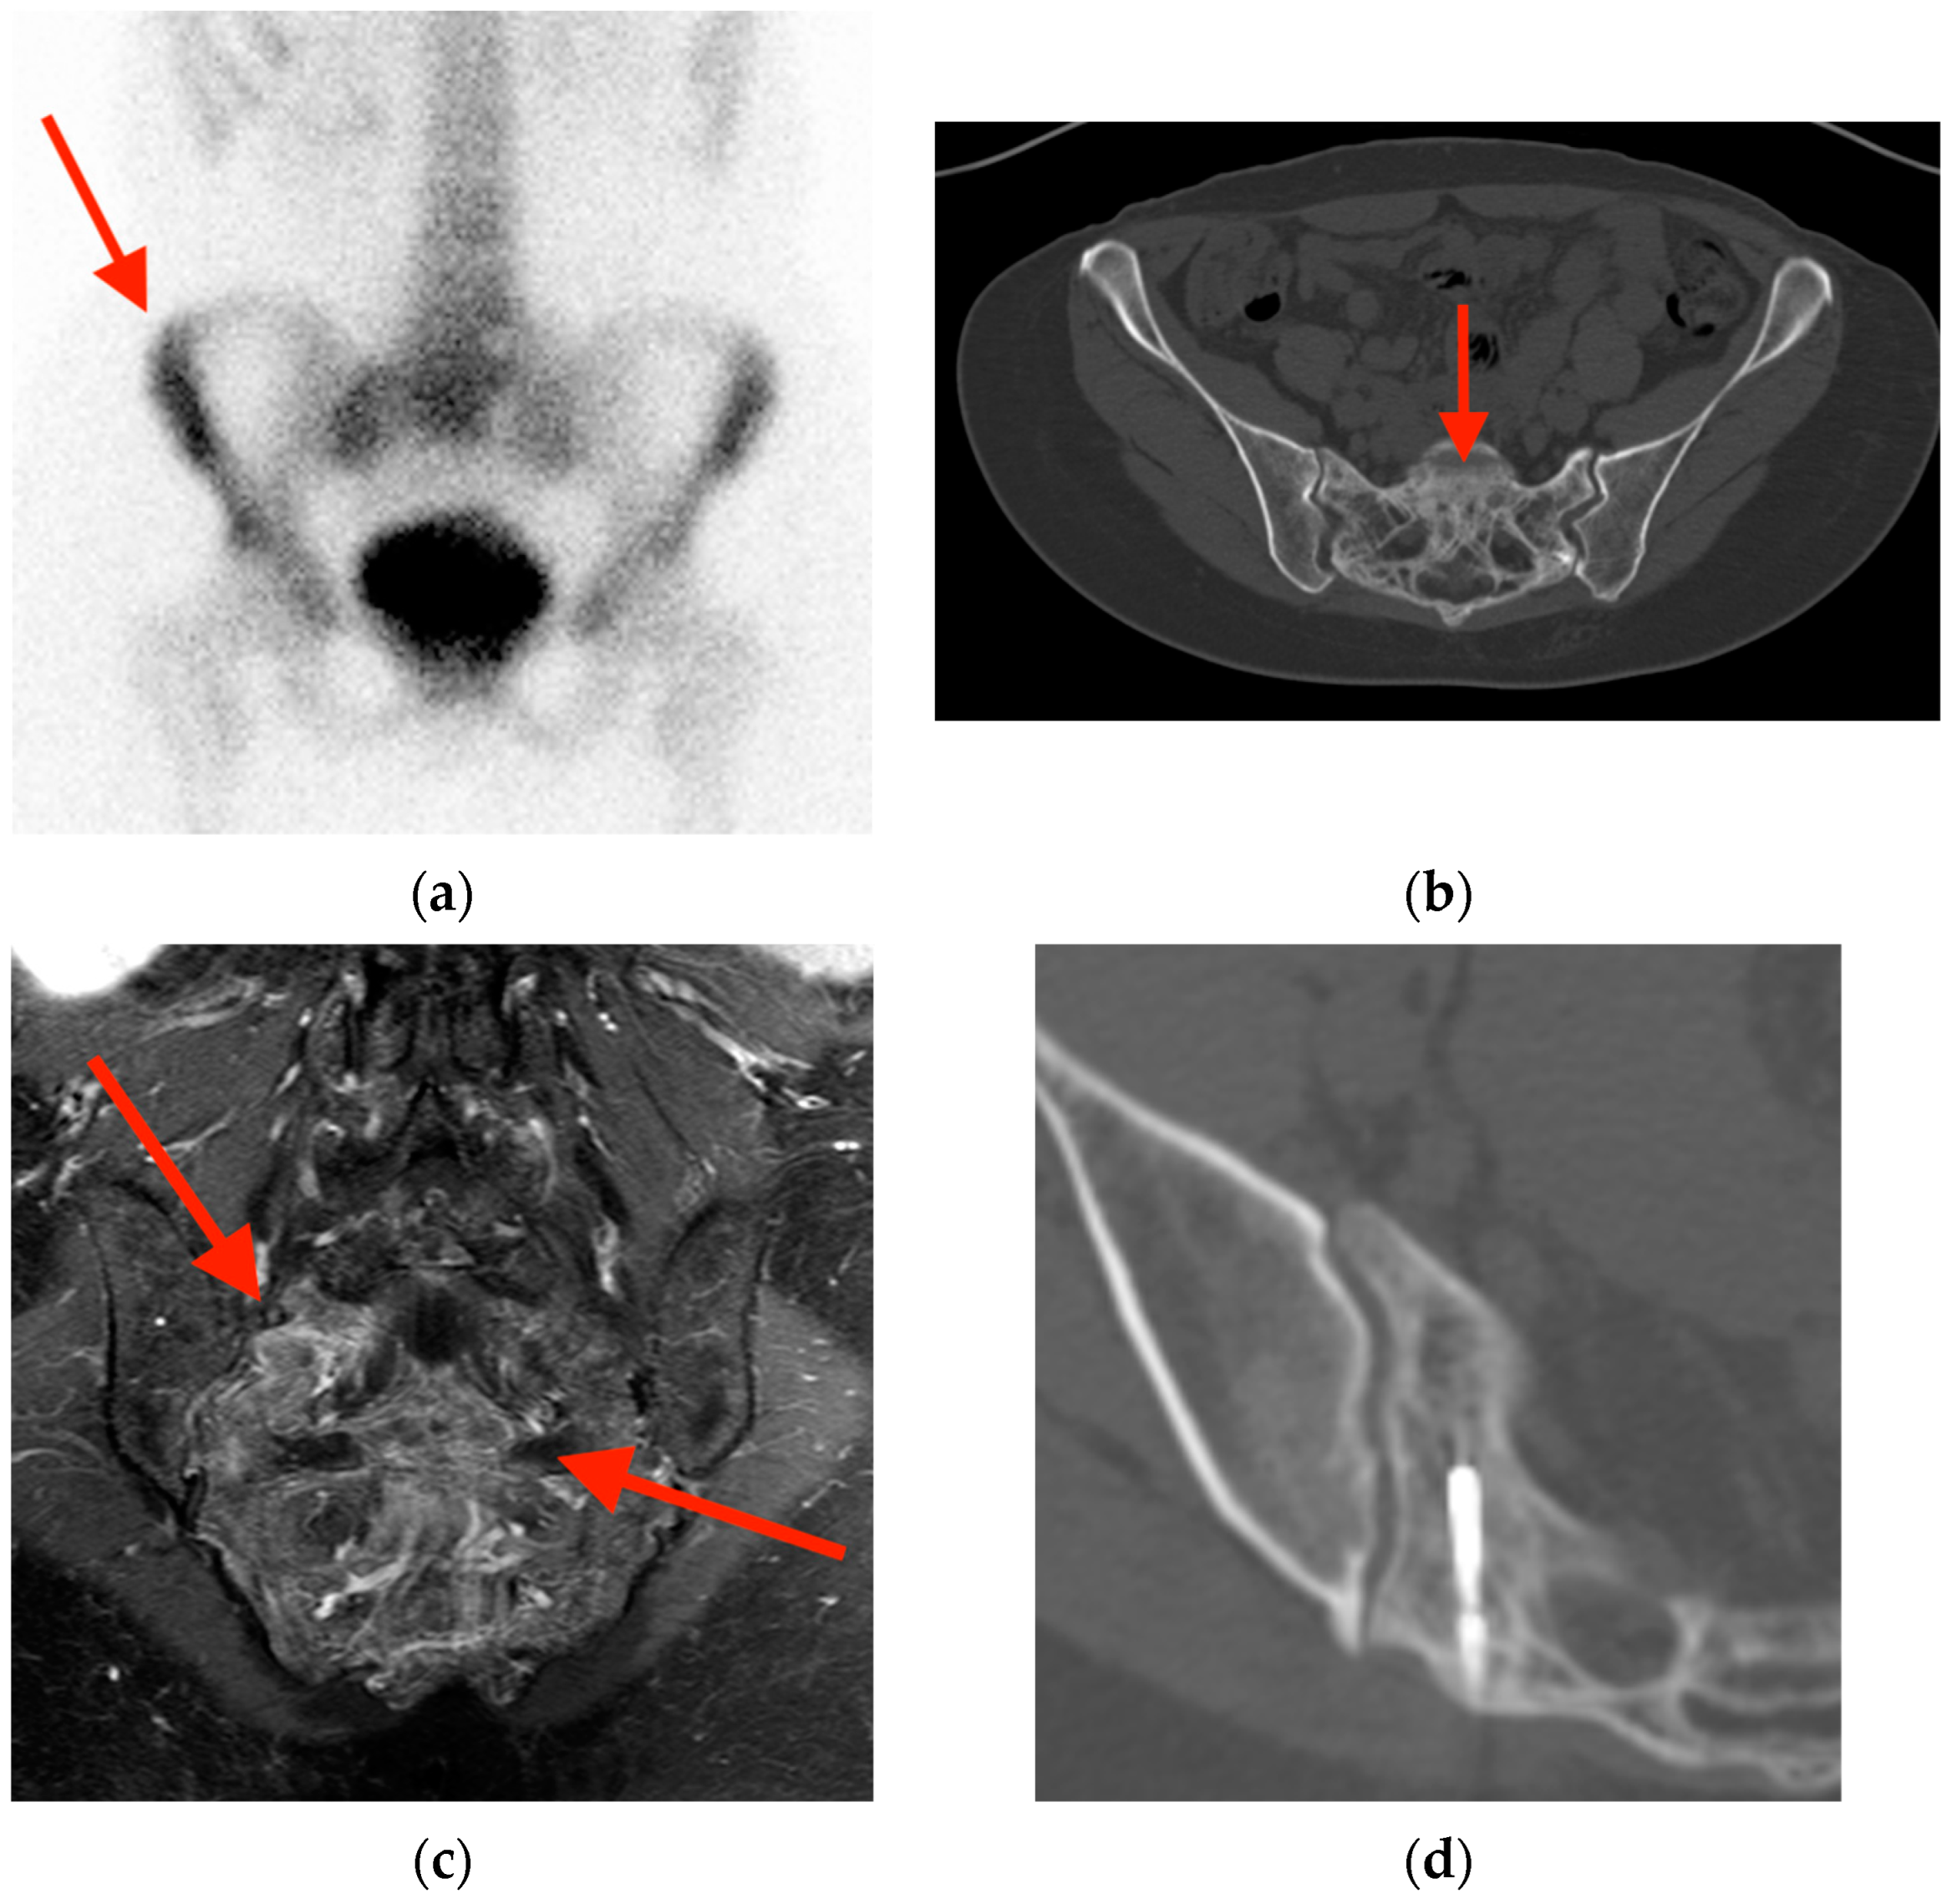

2.1. Fracture

- Oh, D.; Huh, S.J. Insufficiency fracture after radiation therapy. Radiat. Oncol. J. 2014, 32, 213–220. [Google Scholar] [CrossRef]

- Chung, Y.K.; Lee, Y.K.; Yoon, B.H.; Suh, D.H.; Koo, K.H. Pelvic Insufficiency Fractures in Cervical Cancer After Radiation Therapy: A Meta-Analysis and Review. In Vivo 2021, 35, 1109–1115. [Google Scholar] [CrossRef]

- Blomlie, V.; Rofstad, E.K.; Talle, K.; Sundfør, K.; Winderen, M.; Lien, H.H. Incidence of radiation-induced insufficiency fractures of the female pelvis: Evaluation with MR imaging. AJR Am. J. Roentgenol. 1996, 167, 1205–1210. [Google Scholar] [CrossRef]

- Abe, H.; Nakamura, M.; Takahashi, S.; Maruoka, S.; Ogawa, Y.; Sakamoto, K. Radiation-induced insufficiency fractures of the pelvis: Evaluation with 99mTc-methylene diphosphonate scintigraphy. AJR Am. J. Roentgenol. 1992, 158, 599–602. [Google Scholar] [CrossRef]

- Salavati, A.; Shah, V.; Wang, Z.J.; Yeh, B.M.; Costouros, N.G.; Coakley, F.V. F-18 FDG PET/CT findings in postradiation pelvic insufficiency fracture. Clin. Imaging 2011, 35, 139–142. [Google Scholar] [CrossRef]

- Zhong, X.; Zhang, L.; Dong, T.; Mai, H.; Lu, B.; Huang, L.; Li, J. Clinical and MRI features of sacral insufficiency fractures after radiotherapy in patients with cervical cancer. BMC Womens Health 2022, 22, 166. [Google Scholar] [CrossRef]